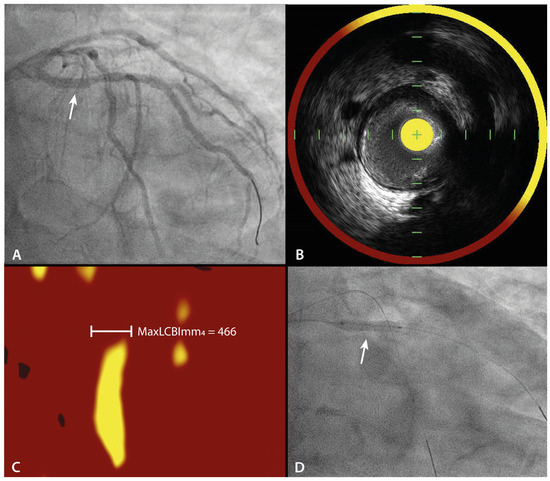

| Change in maxLCBImm4 between baseline and 9 months follow-upin PE-DCB treated LRPs. |